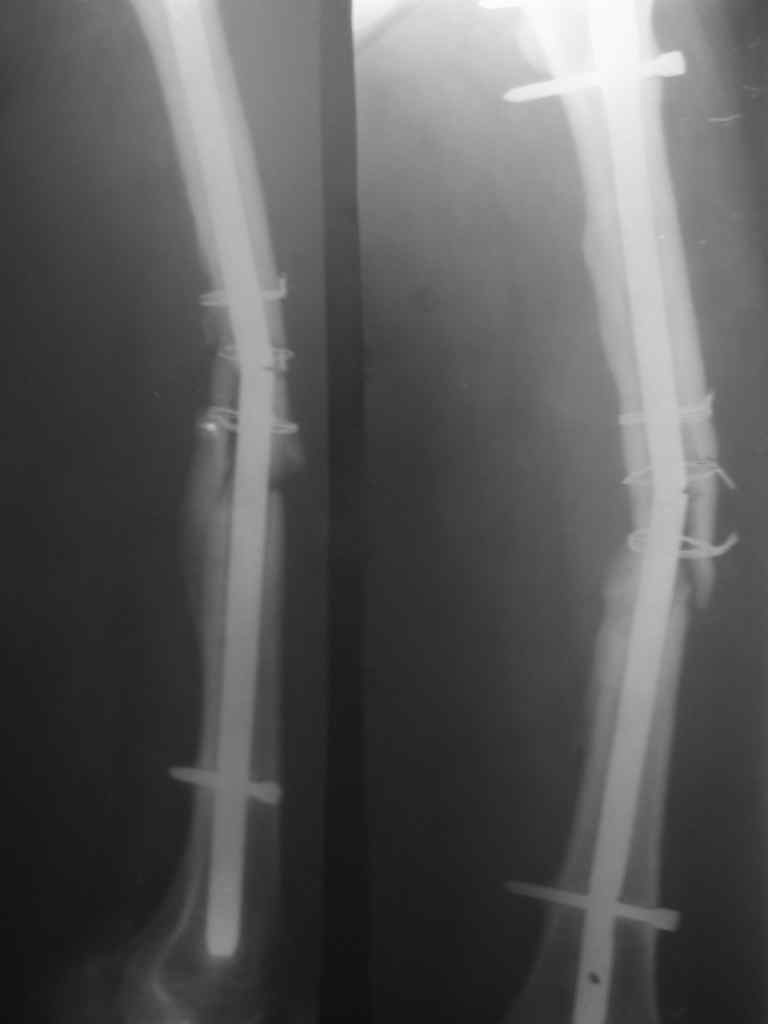

Перелом стержня, серкляж

Поступила молодая,маленькая девочка 18 лет с болями в левом бедре. Из истории:автодорожная травма в ноябре 2005 года, тогда же оперировалась данным способом. Проживает в селе и как правило в таких случаях выпала из поля зрения ведущего доктора.

По нашему мнению возможен реостеосинтез штифтом с рассверливанием более большого диаметра.Но возникают вопросы:

1.Убирать серкляж или нет если получится удалить отломки ChM закрыто.

2.Устранять деформацию бедра АВФ этапно или сразу одномоментно в ДРУ.

3.Блокирование - статическое или динмическое (либо статику на месяц а потом динамизация?)

4.Вопрос о костной пластике и туннелизации.